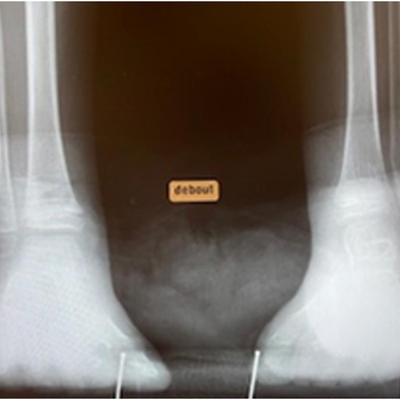

Click on an image below to view more info.